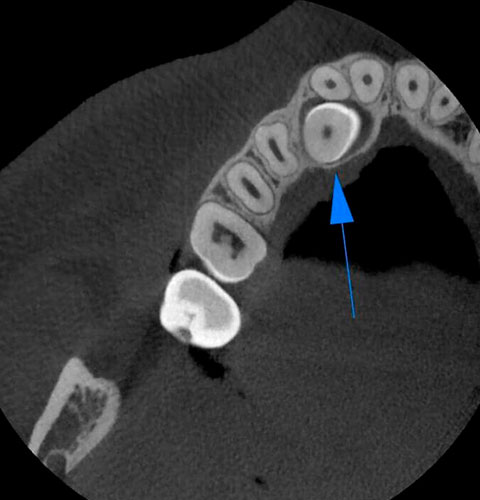

Veja exemplos de diagnósticos de imagem

Com apenas algumas etapas simples, o NNT pode processar os dados adquiridos durante a varredura para criar uma vasta gama de imagens, que fornecem informações detalhadas sobre a anatomia do paciente. Posteriormente, eles podem ser salvos em um relatório ou distribuídos com a versão Viewer do software. O NNT também oferece diferentes modos de aplicação voltados especificamente para implantologia, endodontia, periodontia, cirurgia maxilofacial e radiologia.